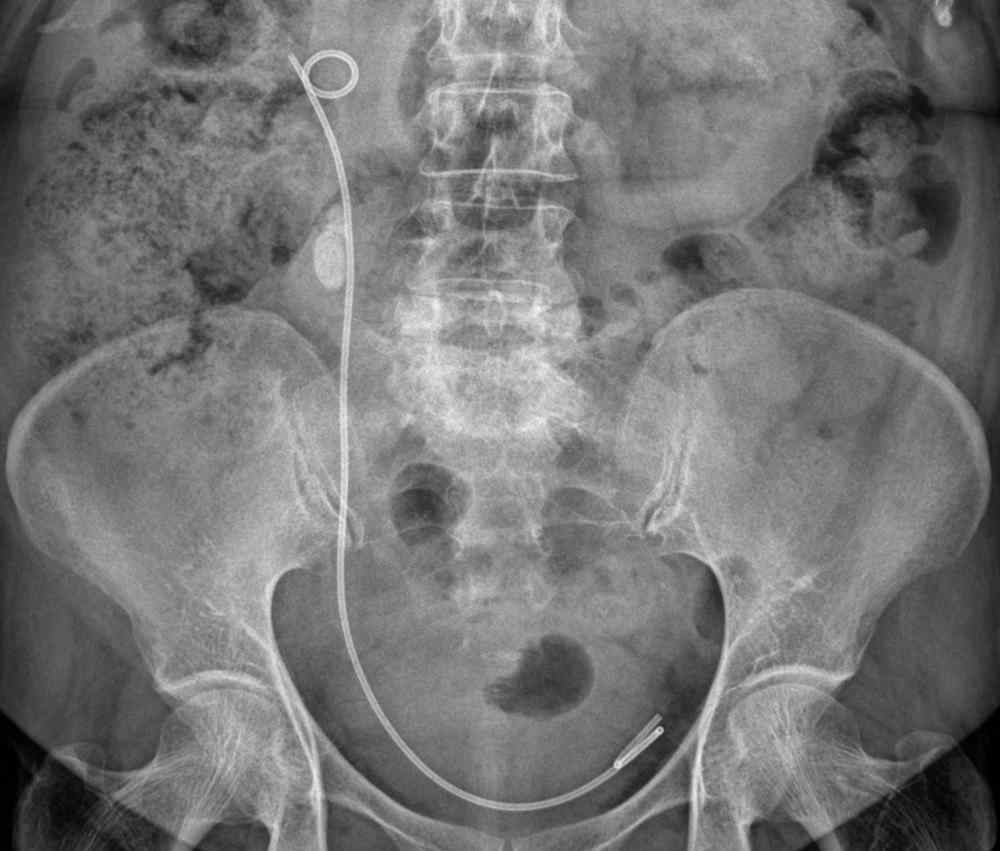

La sonde JJ est un petit tube flexible, généralement en silicone ou en polyuréthane, mesurant entre 24 et 30 cm. Elle assure le passage continu de l’urine du rein vers la vessie. Elle se place dans l’uretère, le canal interne, et non dans l’urètre d’évacuation, une confusion fréquente.

Elle tire son nom de sa forme caractéristique avec deux extrémités recourbées ressemblant à la lettre J. Ce dispositif est placé entre le rein et la vessie, en suivant le trajet naturel de l’uretère.